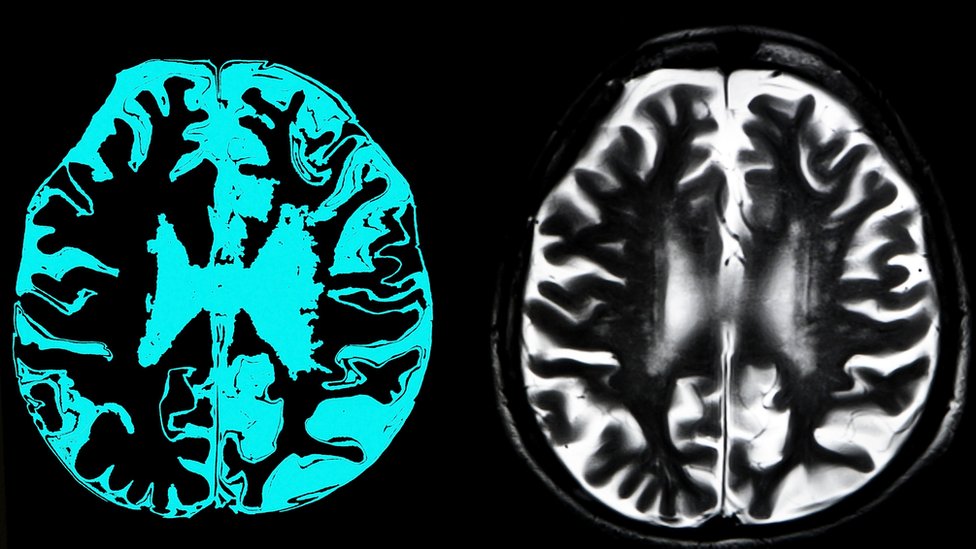

Demencija je stanje koje se ne može u potpunosti sprečiti - starost, genetika i faktori okoline mogu uticati na njen nastanak.